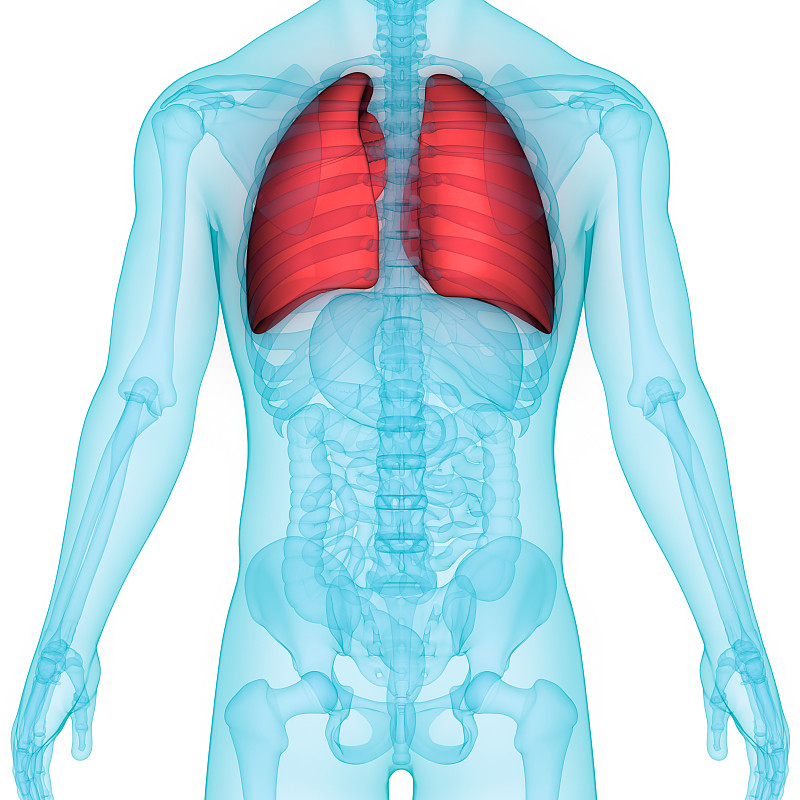

人体呼吸系统肺解剖学详情

JPG